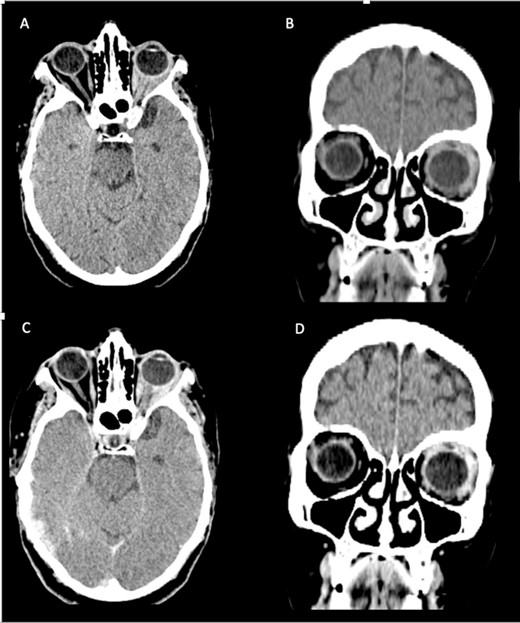

MRI scan showed a lump involving the left superior and lateral extraocular rectus muscles, with slight enhancement along with infiltration of surrounding fat tissue between the ophthalmic nerve and lateral rectus muscle (Fig. 2).

Cerebral and orbital MRI. (A–B) Coronal and axial T2-weighted MRI show iso-intense thickening of the left lateral and superior rectal muscles with fat atrophy. (C) Axial T1-weighted MRI with gadolinium enhancement and fat suppression reveals slight enhancement of the left lateral and superior rectal muscles with infiltration of the surrounding tissues.